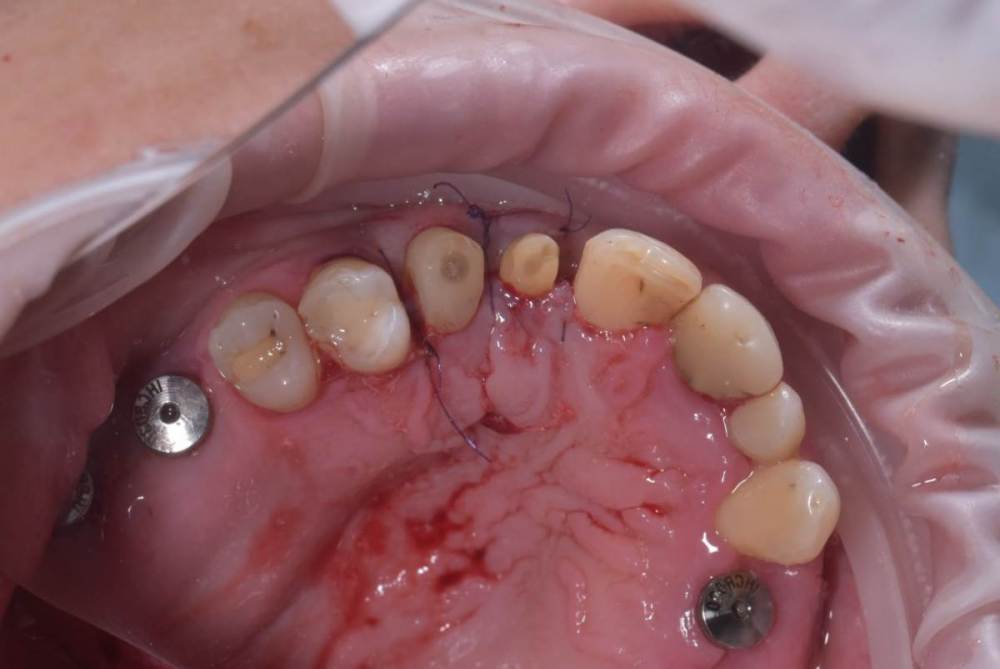

TIGER Опубликовано 3 ноября, 2023 Поделиться Опубликовано 3 ноября, 2023 Периохирургия способна на чудеса)не спешите удалять зубы 5 1 Ссылка на комментарий

АнтонТЛТ Опубликовано 3 ноября, 2023 Поделиться Опубликовано 3 ноября, 2023 А чего зениты не выровнены? Ссылка на комментарий

TIGER Опубликовано 3 ноября, 2023 Автор Поделиться Опубликовано 3 ноября, 2023 @АнтонТЛТ без фанатизма;)всё строго по запросам и финансам пациента Ссылка на комментарий

АнтонТЛТ Опубликовано 3 ноября, 2023 Поделиться Опубликовано 3 ноября, 2023 Ну раз 12 удлинял, то можно было удлинить с аркой зенита и сделать как 22 Ссылка на комментарий

TIGER Опубликовано 3 ноября, 2023 Автор Поделиться Опубликовано 3 ноября, 2023 @АнтонТЛТ Антон честно,лень было)Пациентка довольна как слон,эстетические требования приемлимые.Поэтому не стал навязывать доп манипуляцию.Поэтому тут считаю результат приемлимый Ссылка на комментарий